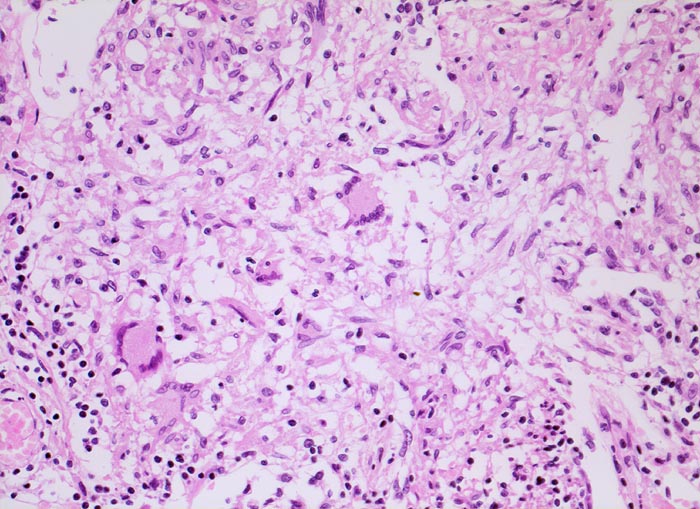

Schlanke spindelige Epitheloidzellen und einzelne Riesenzellen vom Langhanstyp mit peripher hufeisenförmig angeordneten Kernen. Am Rand kleine Lymphozyten.

Die Epitheloidzellen in einem Tuberkulosegranulom sind in der Regel schlank. Die Epitheloidzelle des Sarkoidosegranuloms haben mehr Zytoplasma und plumpere Kerne. Verkäsende Nekrosen kommen allerdings auch bei Sarkoidosegranulomen vor. Vrgl. PathoPic ID 4042